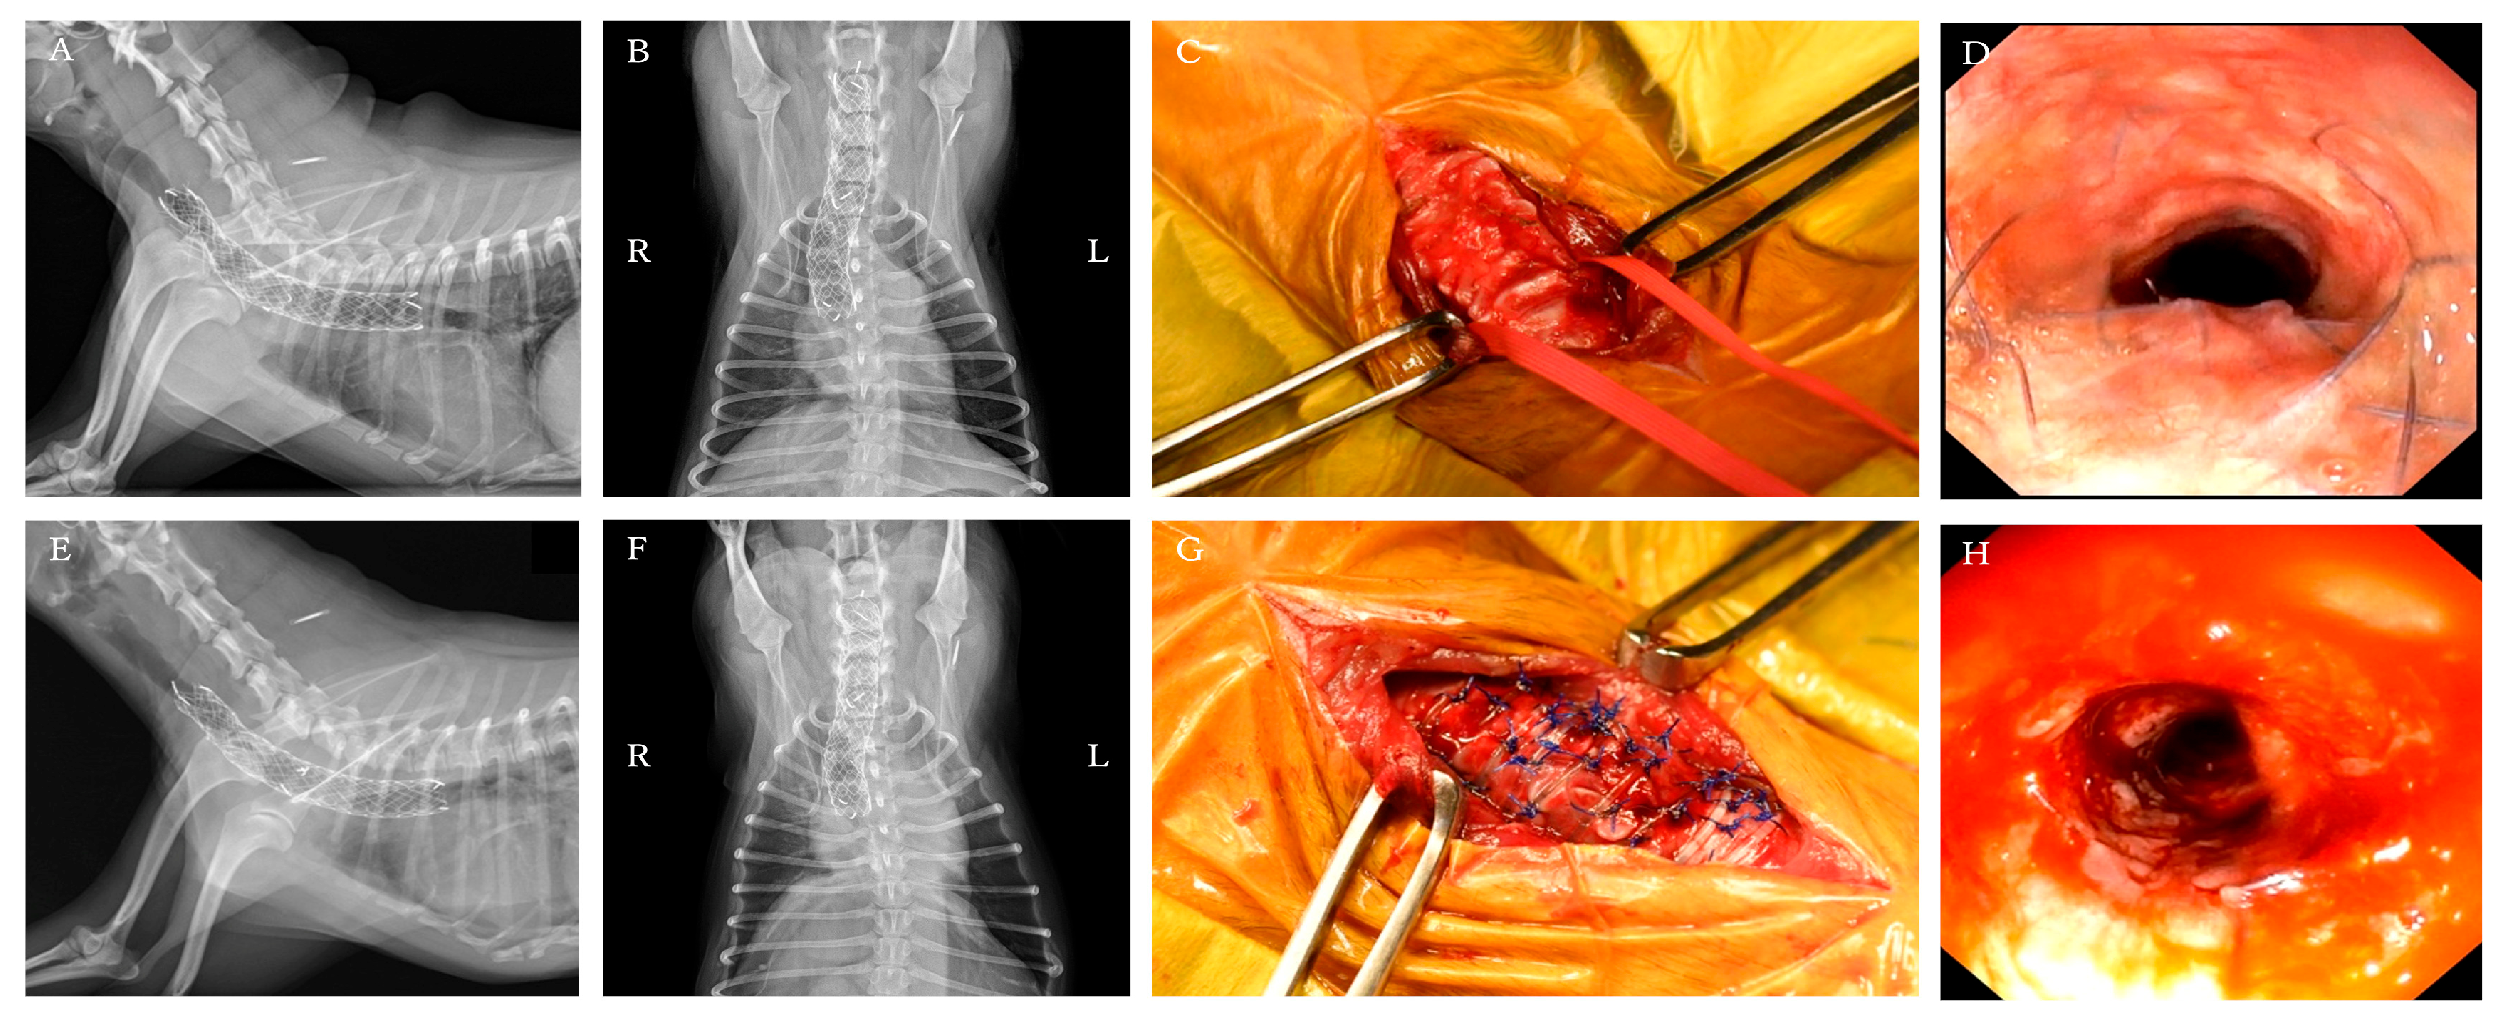

At one year and one month after ELS placement, the patient was re-presented to the hospital with increased coughing frequency and worsening respiratory sounds. Physical examination revealed inspiratory labored breathing and coughing. Radiography and fluoroscopy revealed that the stent had fractured at the tracheal collapse site identified at the initial presented (Figure 4A,B). Additionally, tracheal collapse was observed at the cranial end of the stent. Treatment options considered included placing a new tracheal stent or placing a PLLP. The owner requested PLLP placement, which was performed the following day.

Bronchoscopy revealed that the tracheal stent was entirely covered by granulation tissue, obscuring its structure. At the site of fractured, a portion of the stent protruded into the tracheal lumen (Figure 4D). Additionally, the ventral aspect of the tracheal cartilage was found to be invaginated toward the lumen, resulting in flattening of the tracheal lumen.

A ventral midline approach to the cervical trachea was performed. Dissection was performed while preserving the tracheal blood vessels as much as possible, and the recurrent laryngeal nerves were identified under direct visualization. The fractured area of the stent showed deformation of the cartilage, which had collapsed into the tracheal lumen and flattened (Figure 4C).

A 4-0 Polypropylene Monofilament suture (PROLENE 17 mm 3/8c taperpoint; Johnson & Johnson, Tokyo, Japan) was used for fixation. The ligature was performed by threading the suture through the endotracheal stent as well, thereby pulling the damaged stent while reshaping the tracheal contour. On the ventral side, 3–4 ligations were placed at the fractured site and 2–3 at the non-lesional site. Additionally, one fixation/support suture was added to each ventrolateral side to enhance operability. Pulling the support suture mildly rotated the trachea, allowing ligation of the dorsal loop and reshaping the trachea into a circular form (Figure 4G).

After all sutures were placed, sterile saline was instilled into the trachea to confirm no air leakage from the suture sites. Bronchoscopy revealed the stent protruding into the tracheal lumen had disappeared, and the previously flattened tracheal lumen had clearly improved to a circular shape (Figure 4H).

Figure 4. Pre- and post-placement findings of the PLLP used to manage tracheal stent fracture. (AD) Pre-PLLP placement images. (EH) Post-PLLP placement images. (A) Cervicothoracic radiographs in the right lateral view showing complete fracture of the endoluminal tracheal stent, with associated tracheal narrowing at the fracture site and cranial to the stent. (B) Cervicothoracic radiographs in the ventrodorsal view. (C) Cervical view demonstrating protrusion of a fractured stent segment into the tracheal lumen. Ventral tracheal cartilage invagination was also present, resulting in luminal flattening. (D) Bronchoscopy showing marked deformation of the tracheal lumen at the fracture site. (E) Cervicothoracic radiographs in the right lateral view showing successful reshaping and stabilization of the intraluminal stent. (F) Cervicothoracic radiographs in the ventrodorsal view. (G) Cervical view demonstrating restoration of a near-normal tracheal contour. (H) Bronchoscopy confirming improvement in tracheal luminal shape.